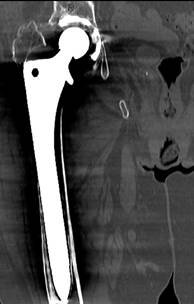

Con respecto al uso de otras pruebas empleadas en el diagnóstico por imagen del aflojamiento, cabe destacar la tomografía axial computarizada (TAC) (Figura 6) y la gammagrafía (Figura 7). Se efectuaron en 36.8% de los pacientes con aflojamiento sin fractura para confirmación diagnóstica de dicho aflojamiento, cuando éste era inconcluyente a través del estudio de radiografías simples (mostrando tendencia, pero no asociación estadísticamente significativa p = 0.062). Cabe reseñar también que no fueron empleadas para la ayuda al diagnóstico en ninguno de los pacientes del grupo de los casos.

Otro aspecto importante lo constituye el apoyo diagnóstico que ofrecen otras pruebas de imagen, concretamente el TAC, resonancia magnética nuclear (RMN) y la gammagrafía. Se trata de pruebas con una alta sensibilidad y especificidad, así como alta eficiencia diagnóstica para el diagnóstico de aflojamientos asépticos;10,11,18 permitieron identificar dicho aflojamiento, especialmente en pacientes en los que el tamaño total sumado en milímetros de las radiolucencias fue escaso.19 Su mayor aplicación y uso en los controles nos habla del papel decisivo que tuvo en muchos de esos pacientes para tomar la decisión de proponer un recambio protésico al realizar un diagnóstico definitivo, protegiendo del riesgo de fractura periprotésica.

La mejor herramienta en la prevención de fracturas periprotésicas en pacientes con vástagos aflojados, la constituye el adecuado diagnóstico precoz del mismo y tratamiento (recambio), antes de que se produzca una potencial fractura. Esto pasa por realizar un adecuado seguimiento clínico y radiológico,2 especialmente en pacientes de sexo femenino y de avanzada edad3 y que refieran importante dolor. Teniendo en cuenta la escasa rentabilidad diagnóstica extraída del análisis exclusivo de las radiolucencias en radiografías simples que evidencia nuestro estudio, así como la escasa rentabilidad de otros hallazgos identificables en las mismas, el empleo de pruebas como la gammagrafía y TAC suponen una herramienta complementaria básica para establecer el diagnóstico18 y ayudarnos en la indicación de un recambio proteico si fuera preciso.